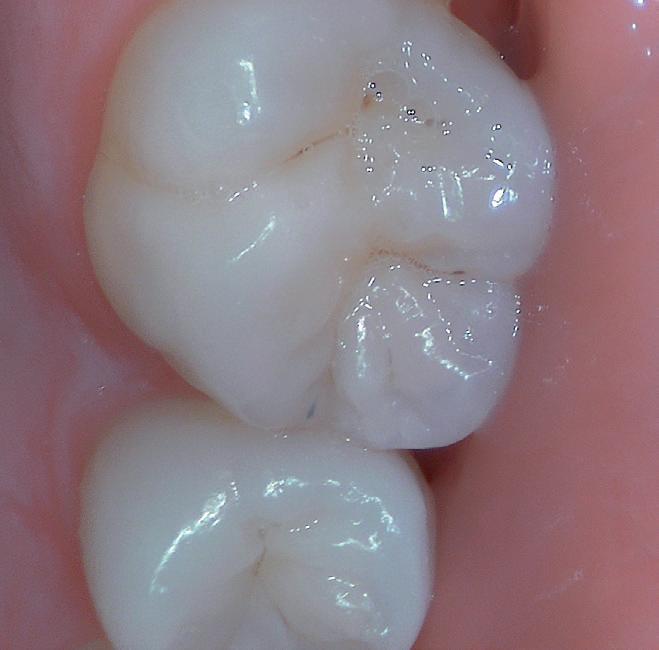

Improved interpretation of tooth shades with rendering of natural colors.

Exclusive macrovision performance

Extreme visibility for ultra-precise diagnosis.

High contrasts emphasizing anatomic fissures and details of the dentin structure/depth.

Daylight or Diagnostic aid modes help you visualize anatomical details that are invisible to the naked eye or with a mirror (thanks to its magnification).